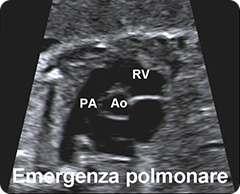

torace:

valutazione e visualizzazione della posizione del cuore e dei polmoni;

visualizzazione delle 4 cavità cardiache, dell'emergenza e incrocio dei

grossi vasi e della scansione 3VT